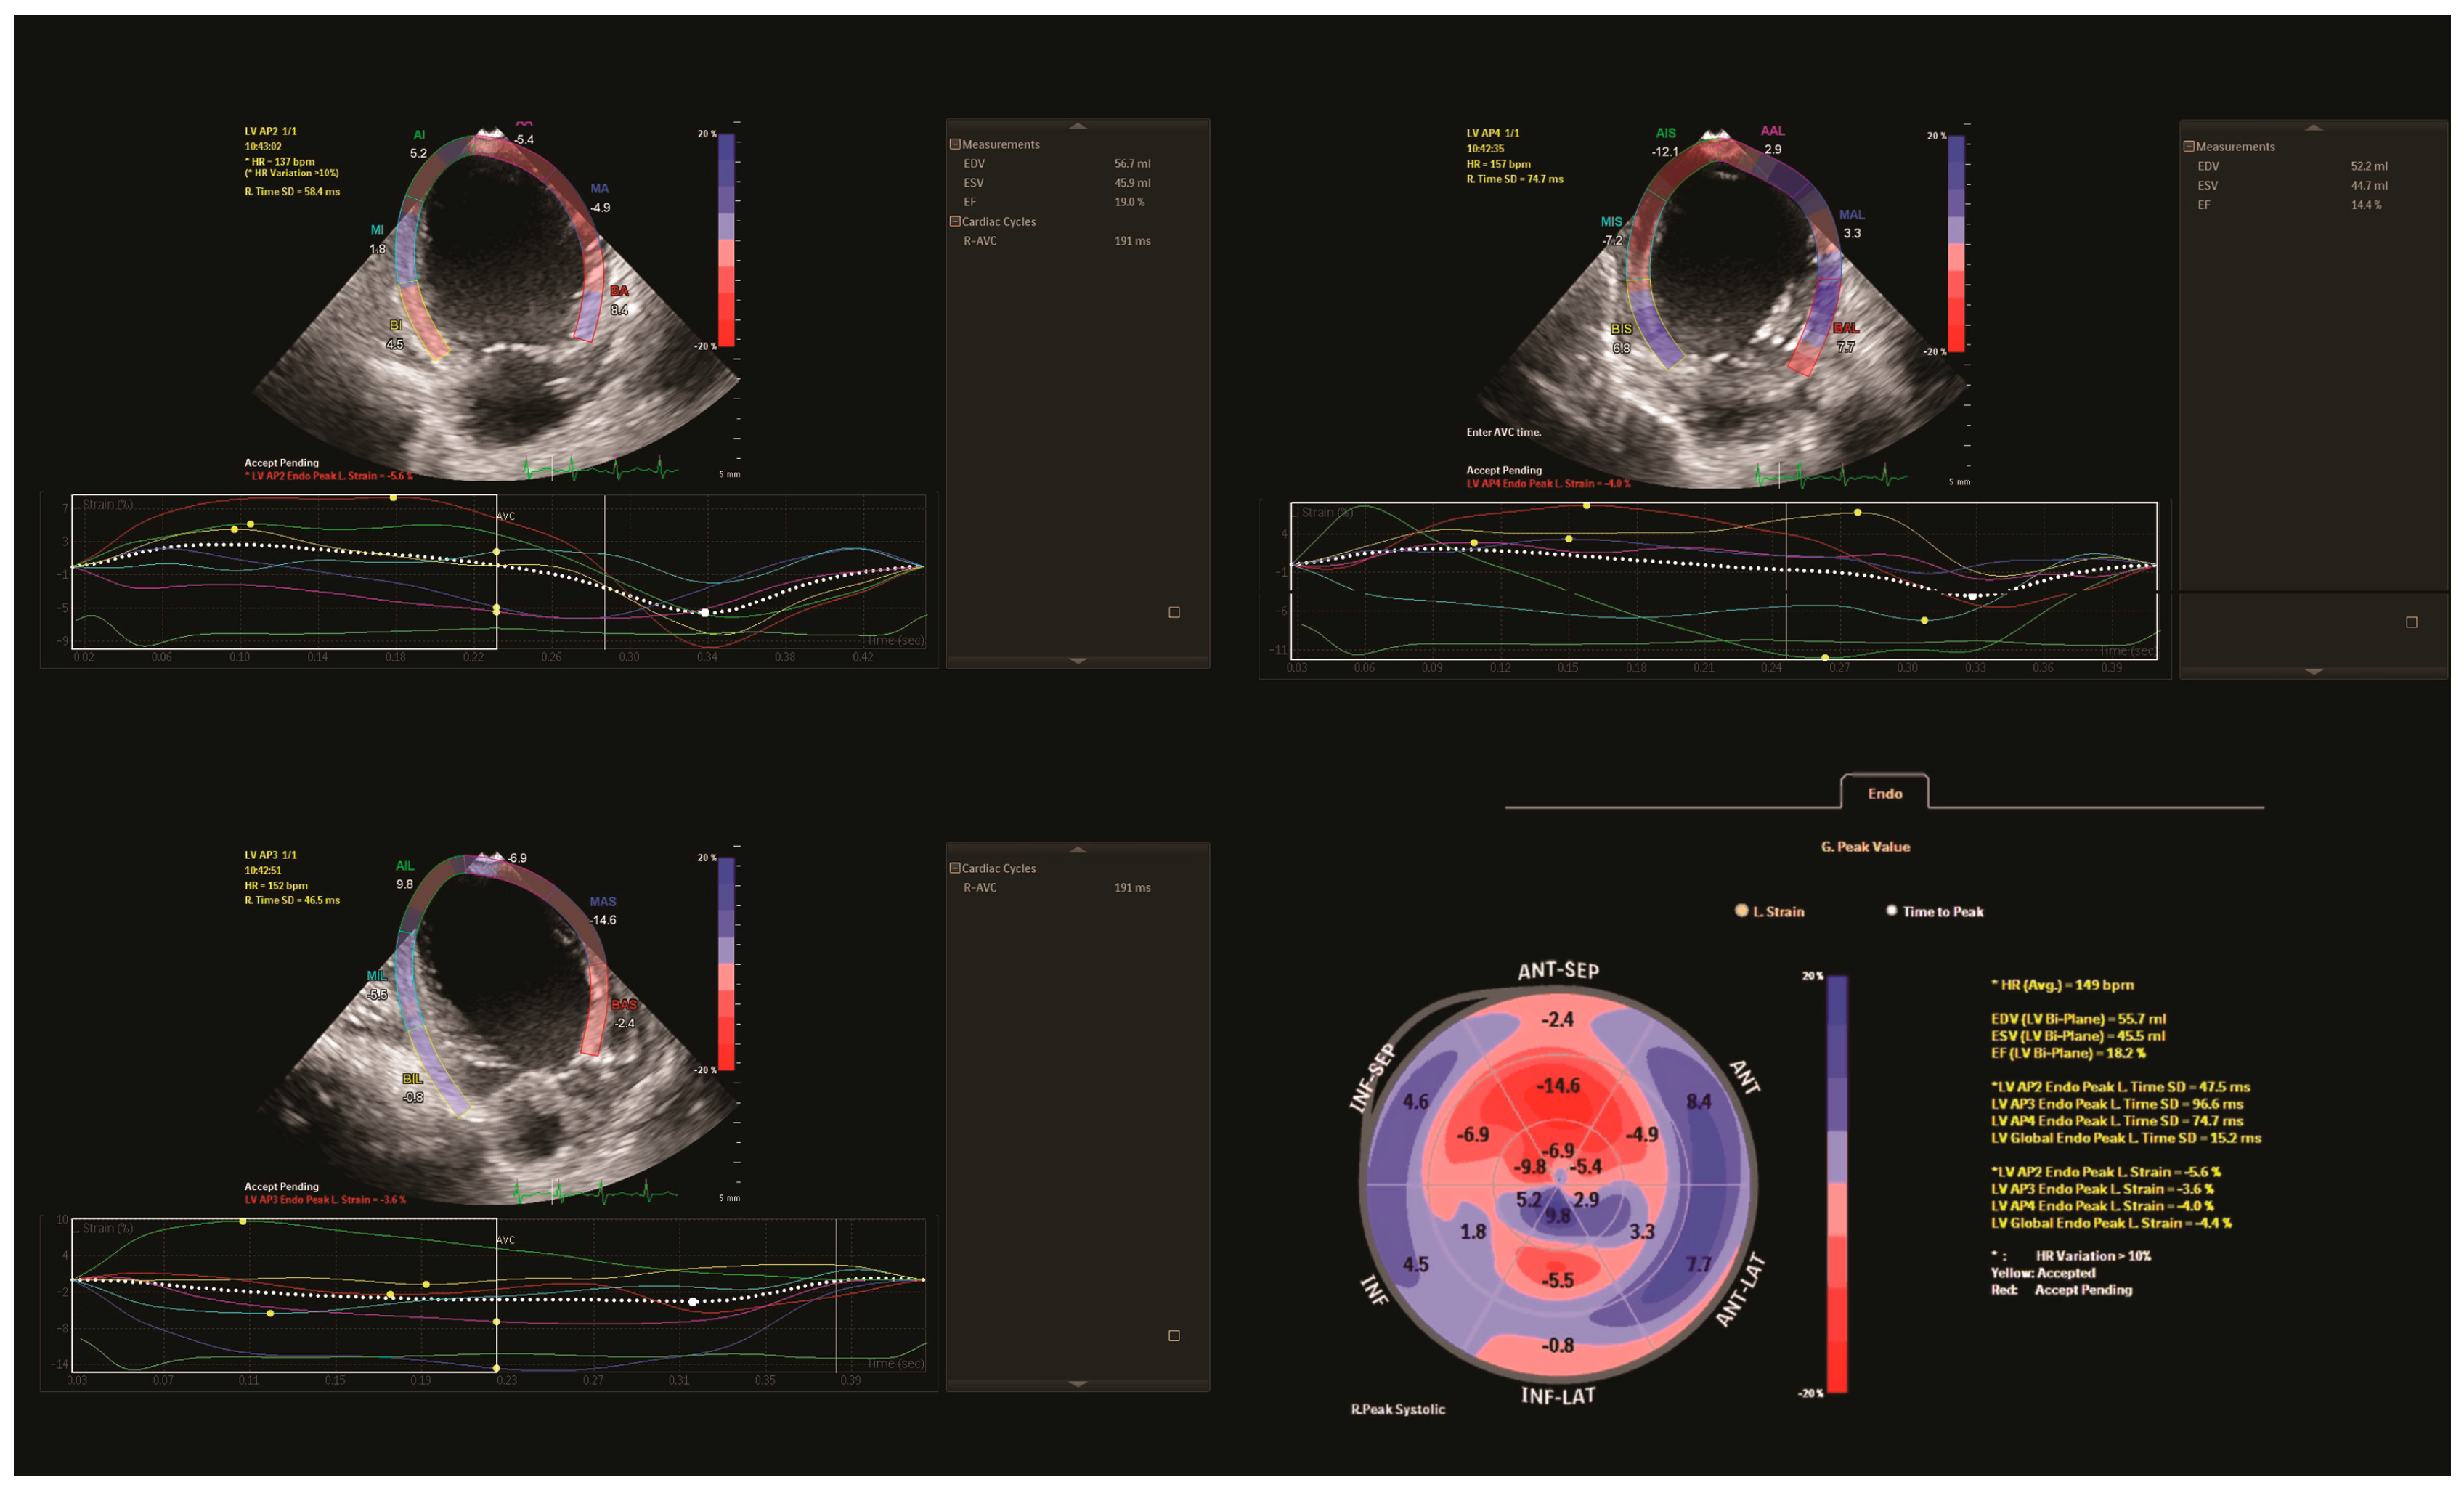

In the postoperative period, the patient was hospitalized in the ICU for 63 days. In the first three days, sternum closure was delayed to stabilise the patient. Also, during the immediate postoperative care, the patient required aggressive treatment for HF, including the administration of various inotropes such as Adrenaline, Milrinone and Levosimendan. Considering the compromised global contractility with persistent LV dilation and dyskinetic interventricular septum, treatment with Adrenaline was continued and tapered off on day 70 postoperatively. In the first 20 days after surgery, laboratory tests revealed a significant decrease in NT-proBNP values (15,000 pg/mL). Furthermore, transthoracic echocardiography confirmed the patency of the new LCA button, a slightly increased LV EF (25%) and GLS (−10). Additionally, there was an improvement in mitral valve insufficiency from severe to moderate. Compared to the preoperative period, the electrocardiogram still showed a QR pattern in lateral leads, albeit with a reduced q wave amplitude. However, infectious complications such as sepsis with Klebsiella BLSE led to a slight reduction in GLS (−5) and LV EF (20%). Also, in the early postoperative period, the patient developed thrombosis in the left atrium, likely due to decreased LV function. Consequently, a continuous infusion of Heparin was administered, followed by Enoxaparin, resulting in complete thrombus resolution. Additionally, pleural and pericardial effusion necessitated pleural drainage and increased diuretic therapy. In evolution, after the tapering of Adrenaline, a combination therapy for HF comprising a Beta-blocker, ACE inhibitor and aldosterone antagonist was gradually introduced. When the patient was discharged, laboratory tests revealed a significantly lower NT-proBNP value (7226.4 pg/mL) and the speckle-tracking analysis indicated improvement in regional and GLS (−7.9%) compared with the initial measurements, with an LV EF of 30% (Table 1).

However, some of the LCA-supplied segments remained impaired (Figure 3).

Figure 3. Compared to preoperative echocardiography, follow-up 2D echocardiography showed a mildly dilated left ventricle, with reverse remodelling after surgery (A,B). Follow-up speckle tracking analysis revealed that postoperative global longitudinal strain increased compared to preoperative analysis, with normal global longitudinal strain in right coronary artery territories. At the same time, mechanical dyssynchrony remained in some segments supplied by the left coronary artery (C,D).